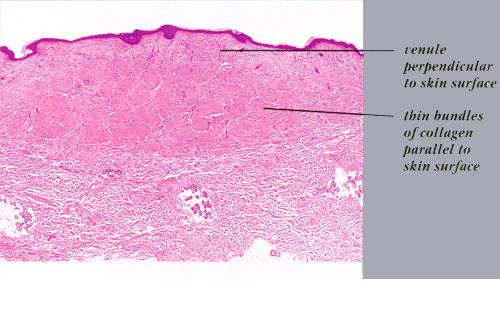

Hypertrophic Scar = ندبة ضخامية